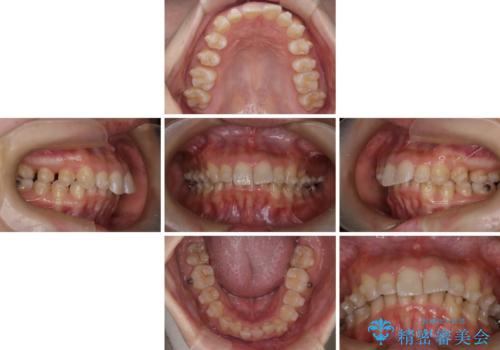

- 上の前歯の出っ歯と前歯の深い咬み合わせを治したいとのことで来院された患者様です。

上顎の歯は後方移動とIPR(歯と歯の間を削る)によって口元が引っ込むように、下顎は歯列全体の拡大とIPRによって上顎とバランスよく咬み合うように設計し、インビザラインにより治療を行うこととしました。

上顎歯列の後方への移動量が多く、右側の奥歯の咬み合わせを改善する必要もあったため、治療には長期間を要しました。